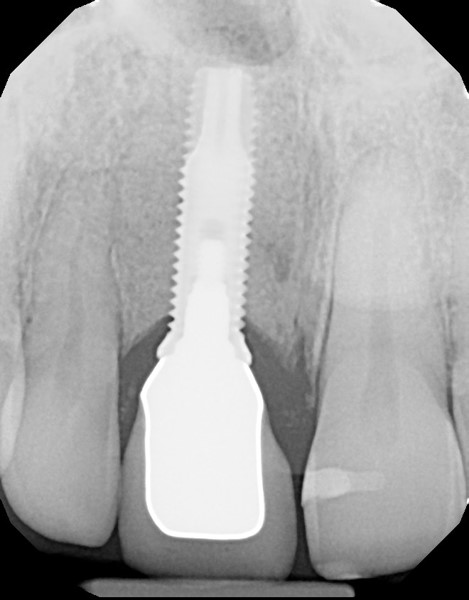

Fig 11. The success and efficacy of this approach was confirmed radiographically at 8 years post-treatment, as demonstrated by the stable gingival margins, thickened biotype with a connective tissue graft, and stable bone levels observed at the first thread of the fixture.

Figure 11

At 8 years post-treatment, implant bone levels were maintained as evidenced radiographically (Figure 11), with stable gingival margins and bone levels at the first thread of the fixture. There was minimal visible damage and scar tissue from the surgical approach to implant placement and tissue grafting to thicken the biotype. Despite the potential challenges, the use of growth factor technology and minimally invasive surgical techniques allowed the esthetic treatment goals for this case to be achieved for the long term (Figure 12).